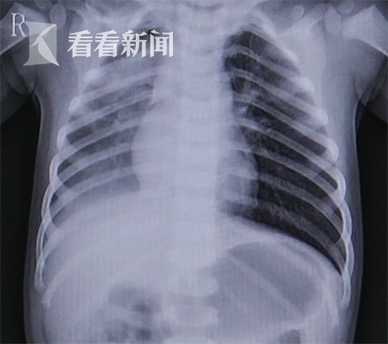

视频|1岁半男童开心果吸入肺部致咳血 家属以为

388x344 - 10KB - JPEG